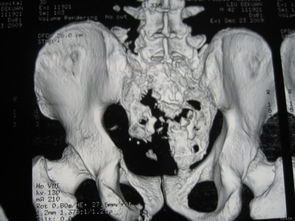

骶尾骨骨折要休息多長時間會好呢,在這期間骨折患者應(yīng)該如何注意自己的飲食呢?那么,請點(diǎn)擊馬上鏈接康復(fù)熱線 骶神經(jīng)損傷嚴(yán)重時可出現(xiàn)跟腱反射消失,但很少出現(xiàn)括約肌功能障礙,予后與神經(jīng)損傷程度有關(guān),輕度損傷予后好,一般一年內(nèi)可望恢復(fù)。